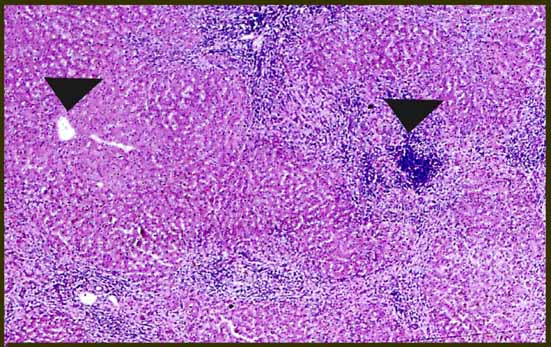

fig. 6

Figura 6.- Masson 100X; Intensa fibrosis extendiéndose por los sinusoides con escasa inflamación.